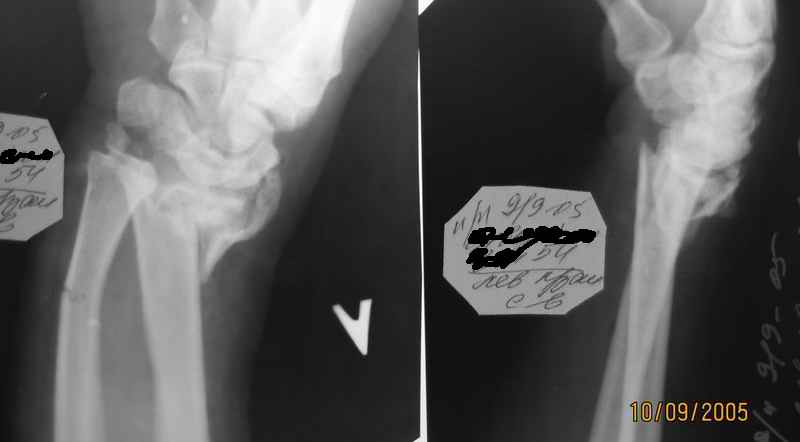

Уважаемые коллеги. Мужчина 54 года, поступил накануне-открытый перелом луча

Падение с высоты собственного роста. Перелом открытый, рана поверхностная на ладонной поверхности в проекции метэпифиза лучевой кости 1,5 см. Дежурной бригадой ПХО раны, попытка ручной репозиции, на контрольных снимках смещение остается (снимки очень низкого качества, поэтому не представляю). Какой вариант оперативного лечения лучше избрать? С уважением А. Минервин.

Мыльников Алексей 10 Сентябрь 2005, 17:25

на мой взгляд доступом по тыльно боковой пов-ти луча открытая репозиция, остеосинтез пучком спиц. Но по тем снимкам видно что и локтевая тоже сломана. Да, и ещё вопрос рана при ПХО ушита наглухо?

Абсалютное показание к внеочаговому дистракционному остеосинтезу аппаратом Илизарова за пястные кости. Судя по рентгенограмм :

Полифрактура. Откр. внутрисуставной оскольчатый перелом дистального конца лучевой кости и перелом шиловидного отростка и диафизарный перелом локтевой кости со смещением костных отломков. Для достижение идеального устранение смещений костных отломков (что очень важно для дальнейшего воостановление функции лучезапстного сустава) предлагаю по новой методики нашей клиники.

По рентген у луча "минус" вариант и это отрицательно будет высказываться на функции лечезапятсного сустава, т.е. у больного ограничение локтвеой девиации кисти.